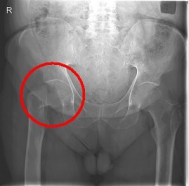

Femoral Neck Fracture

The femoral neck fracture is one of the most common fractures of the elderly. The cause is usually a fall on the hip from a low height. An important risk factor is osteoporosis.

In addition to a thorough physical examination, radiographs of the pelvis and the affected hip are crucial for the diagnosis.

Images: Here is the supply of a dynamic hip screw shown.

In younger patients and a minor shift, the goal is to preserve the femoral head. The blood supply to the femoral head is at risk for medial femoral neck fractures, so that the fastest possible care should be sought if one wants to preserve the femoral head. Among others, the dynamic hip screw (DHS) is available for this purpose.